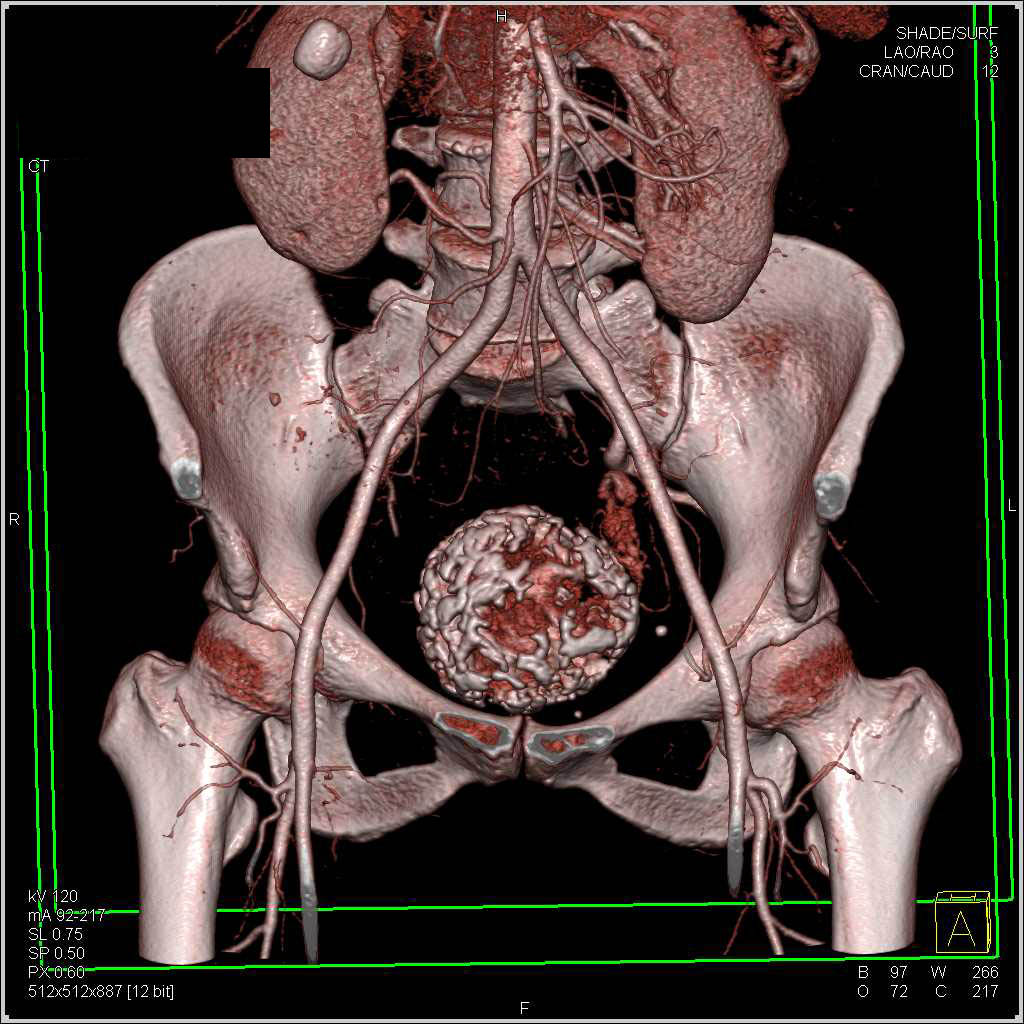

Calcified Fibroid – OB/GYN Case Studies – CTisus CT Scanning

Calcified Uterine Fibroids / CTisus.com | Uterine fibroids, Fibroids …

Calcified Uterine Fibroids – OB/GYN Case Studies – CTisus CT Scanning

Pelvic MRI for Fibroids – Why You Need an MRI to Detect Fibroids